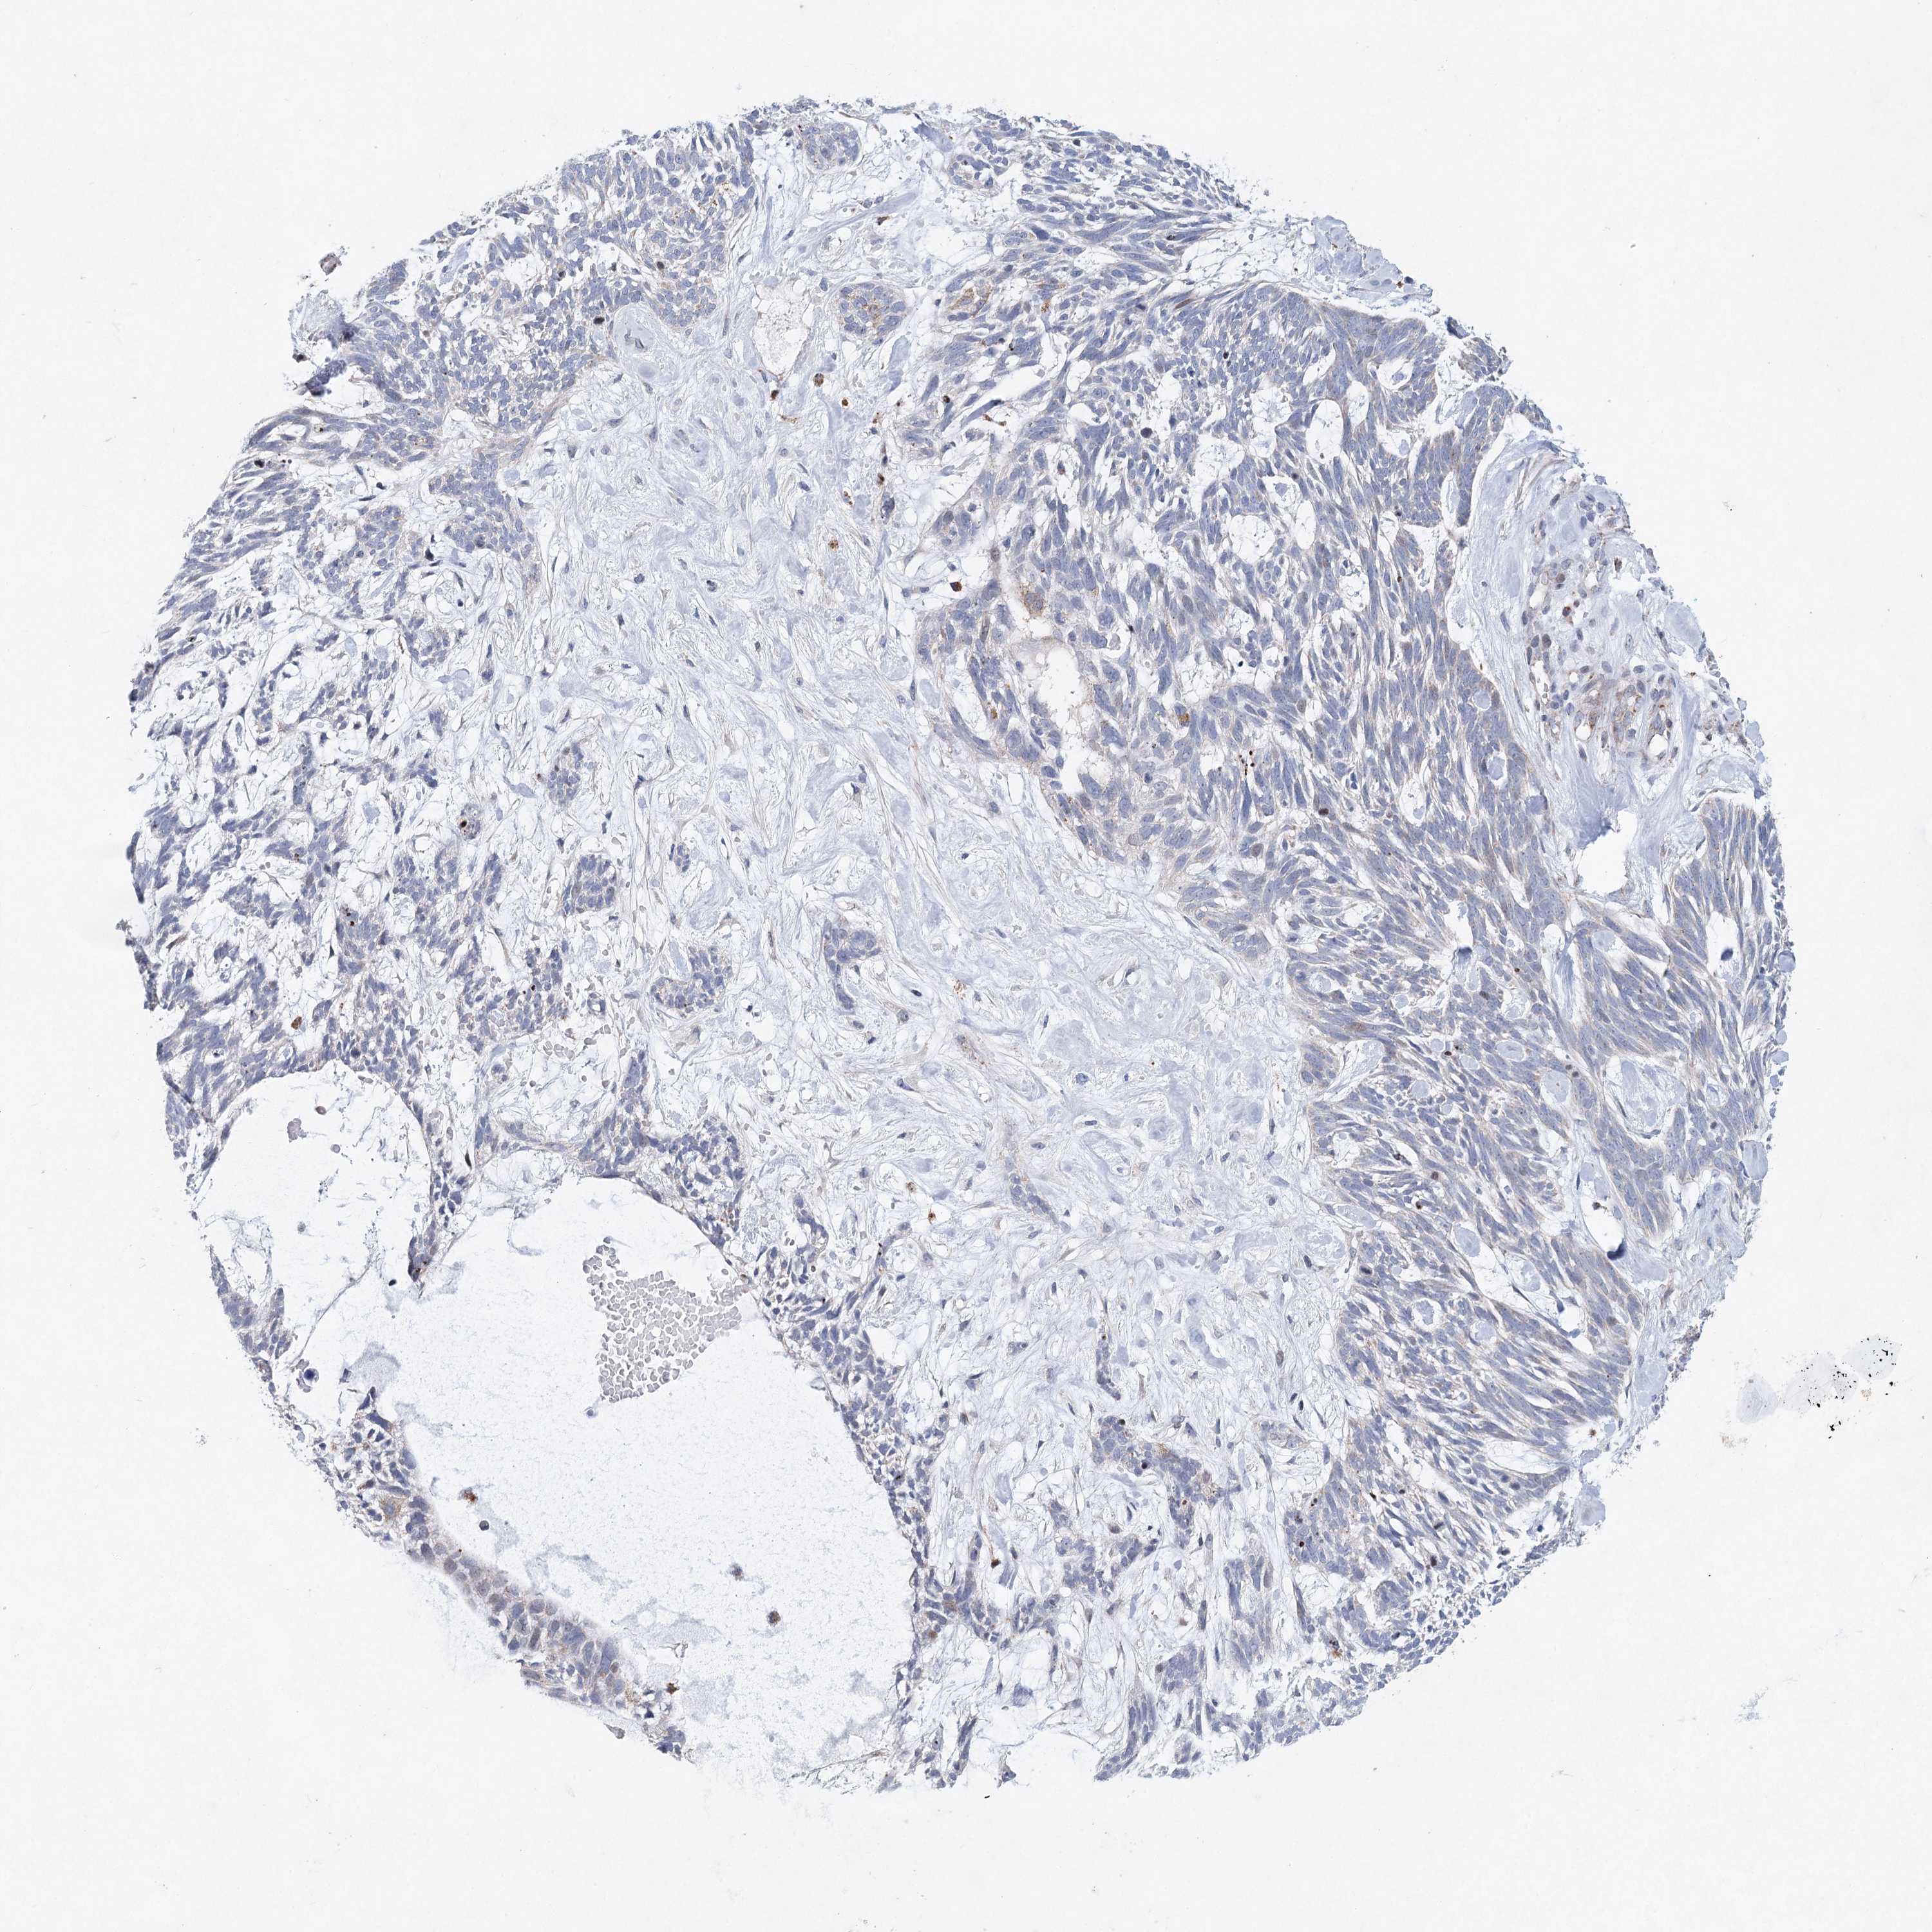

SKIN CANCER - Protein expressioni

A mouse-over function shows sample information and annotation data. Click on an image to view it in a full screen mode. Samples can be filtered based on level of antibody staining by selecting one or several of the following categories: high, medium, low and not detected. The assay and annotation is described here.

Antibody stainingi

Antibody staining in the annotated cell types in the current human tissue is reported as not detected, low, medium, or high, based on conventional immunohistochemistry profiling in selected tissues. This score is based on the combination of the staining intensity and fraction of stained cells.

Each image is clickable and will lead to virtual microscopy that enables deeper exploration of all samples and also displays staining intensity scores, fraction scores and subcellular localization as well as patient and tissue information for each sample.

Antibody HPA038246

Staining

High

Medium

Low

Not detected

Intensity

Strong

Moderate

Weak

Negative

Quantity

>75%

75%-25%

<25%

None

Location

Nuclear

Cytoplasmic/membranous

Cytoplasmic/membranous,nuclear

Squamous cell carcinoma, NOS

Squamous cell carcinoma, metastatic, NOS